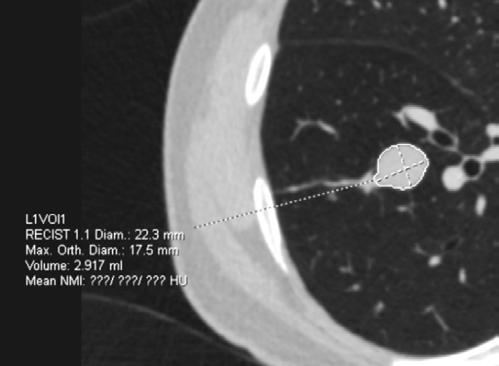

Figura 1-4. Estudio de tomografía simple de tórax, con reconstrucción volumétrica, multiplanares con ventana para pulmón y en mediastino (, en donde se observa el nódulo pulmonar sólido de bordes lobulados hipodensos.

Se le realiza estudio de tomografía simple de tórax en donde se encontró en el segmento anterior del lóbulo inferior derecho nódulo sólido, con diámetro de 22mm, volumen de 2.9ml, condiciona disminución del bronquio segmentario, con secreciones endoluminales distales, de acuerdo a la clasificación de LUNG RADS con categoría 4B, alta sospecha de malignidad. Sin evidencia de lesiones nodulares en el resto del parénquima.

El sistema LUNG RADS para la evaluación de nódulos pulmonares observados en TC de tórax de baja dosis, establece categorías del 0 al 4, dividiendo ésta última en 4A, 4B y 4X, en el caso de los nódulos 4B se establece que son nódulos sólidos con diámetro de 15 mm en el estudio basal o nódulos subsólidos con porción sólida de 8 mm, en la versión actualizada del 2022, se agregan quistes aéreos atípicos con engrosamiento mural o componente nodular mural. La recomendación para esta categoría es la realización de PET CT y/o toma de biopsia.